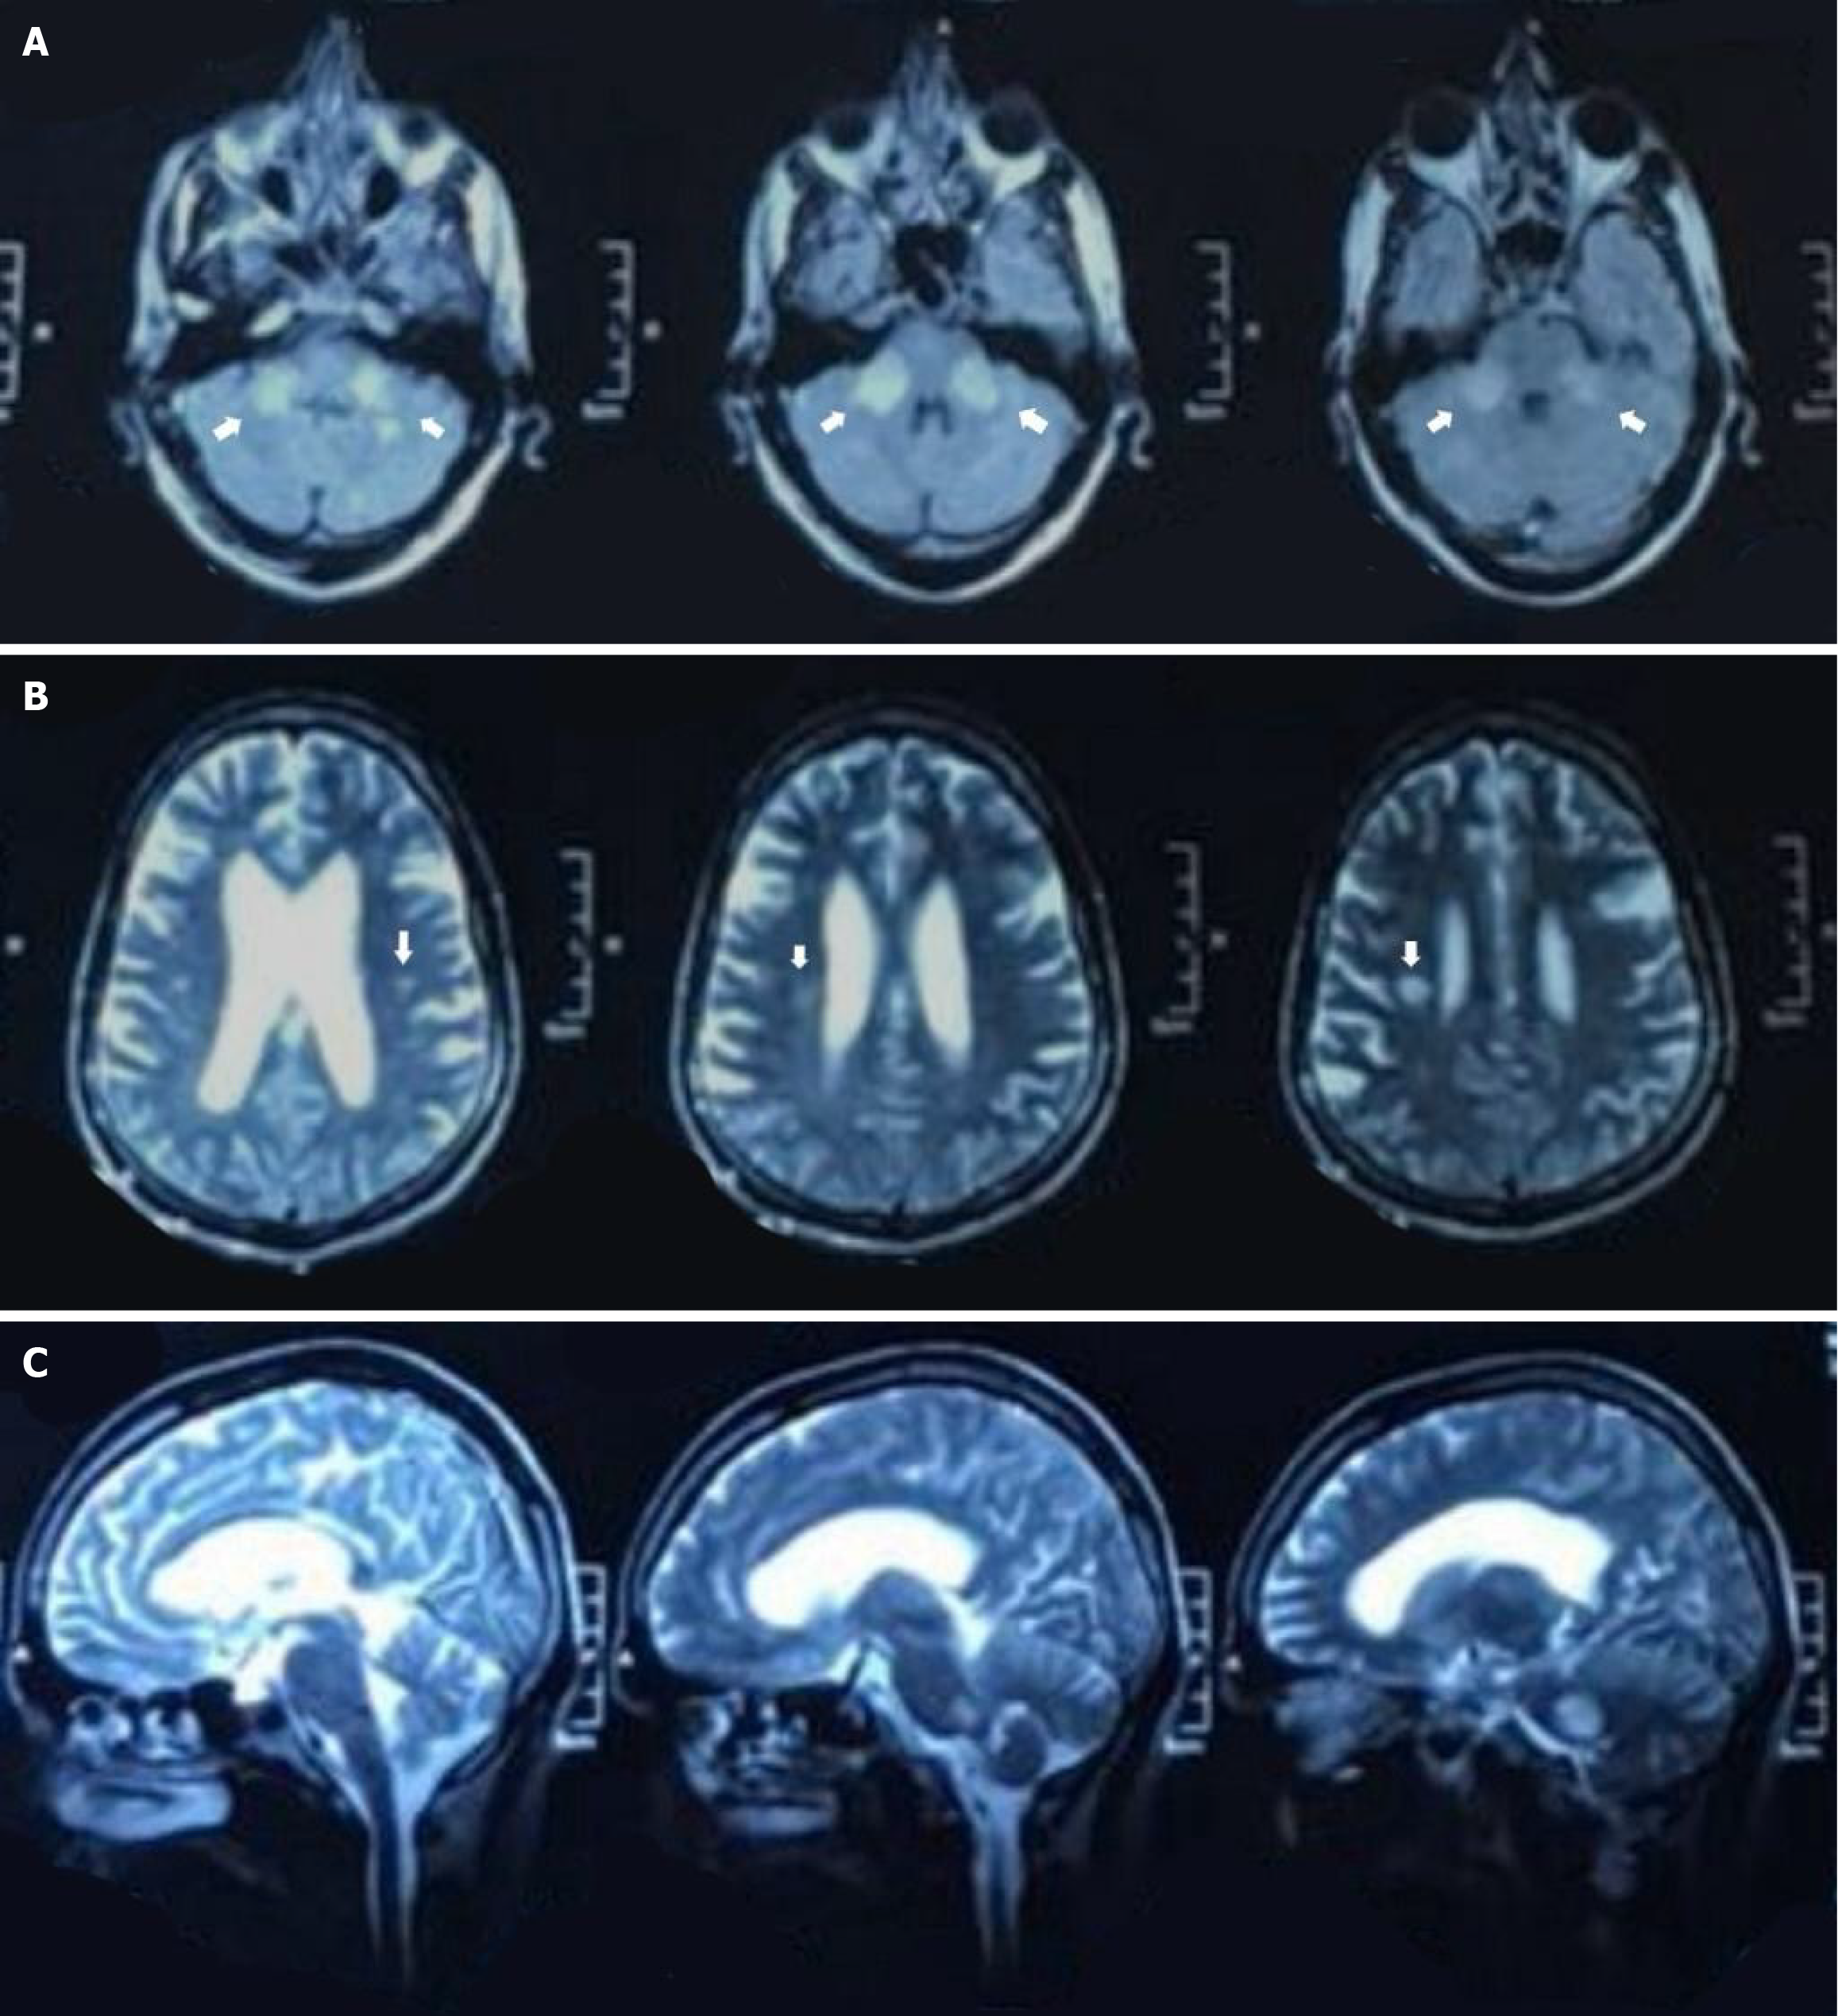

Figure 1 Neuroimaging.

A: Axial T2-weighted magnetic resonance imaging (MRI) demonstrating bilateral, symmetrical hyperintensities in the middle cerebellar peduncles; B: Axial fluid-attenuated inversion recovery MRI image showing subtle periventricular white matter hyperintensities without mass effect or enhancement; C: Sagittal T2-weighted MRI view highlighting lesion distribution involving the brainstem and cerebellum.